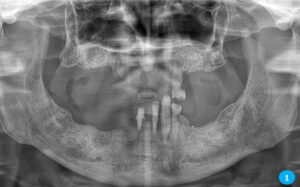

İmplant, ağızda eksik olan dişlerin yerini tutmak üzere, hem fonksiyon hem fonetik ve hem de estetik açıdan boşluklara yerleştirilen ve titanyumdan üretilmiş yapay diş kökü olarak tanımlanabilir.

Alt-üst damakta hiç dişi olmayan hastalar hareketli proteze alışamamakta, bulantı reflefsi oluşturmakta ve çoğu hastada damaklar ağızda sıkı bir şekilde durmamaktadır. Bu durum hastaları sosyal yönden olumsuz etkilyebilmektedir. Hiç dişi olmayan hastalara implant önemli bir çözüm oluşturmaktadır.